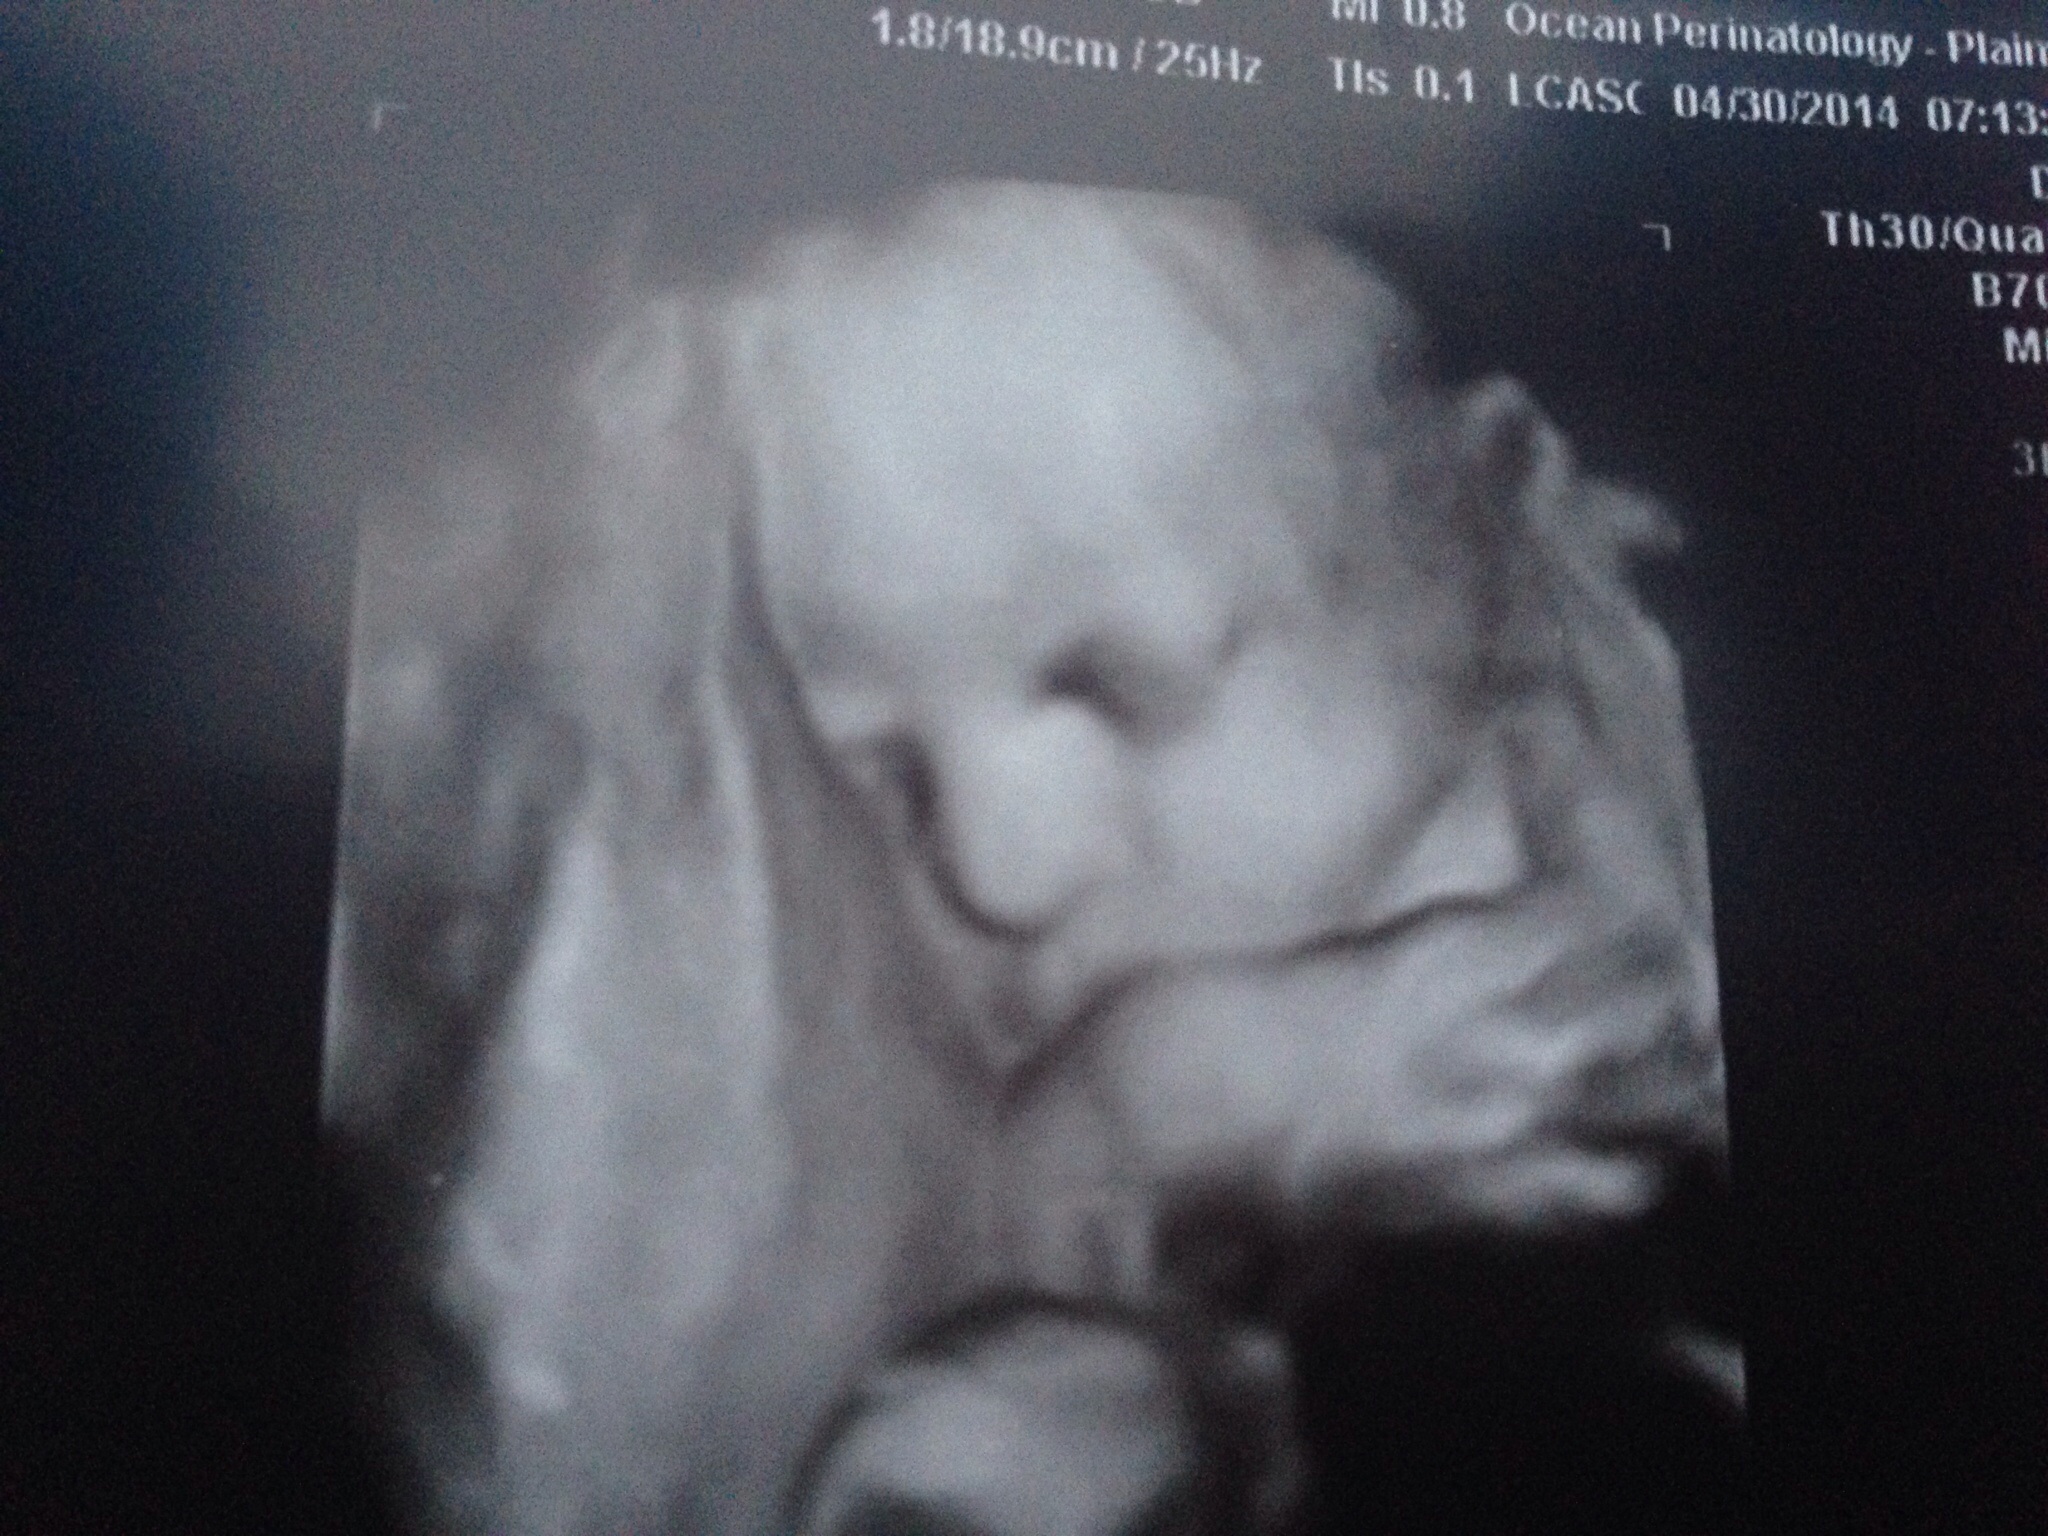

Had a 32 week growth scan this morning. Baby girl is head down, weighing approx 5.5 lbs and everything is looking good. I even got a 3D shot (included below for a little sunshine on this gloomy day of news for our board) Hope everyone has a wonderful day xo

@jenn72178 , that photo is adorable! Looks like it's face is pressed against a glass window haha super cute!